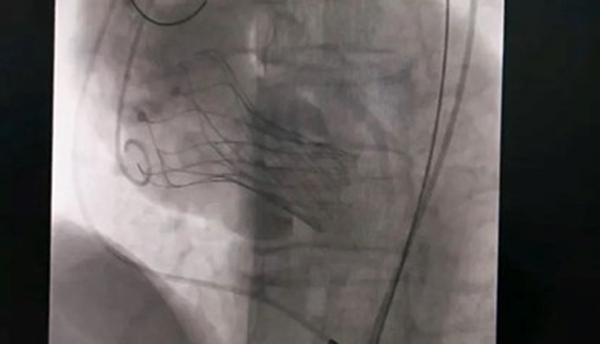

10月18日,該患者實(shí)施手術(shù),在新橋醫(yī)院專家的指導(dǎo)下,心血管內(nèi)科主任宋明寶帶領(lǐng)團(tuán)隊(duì)把瓣膜置入心臟。

人工瓣膜置入中。重慶西區(qū)醫(yī)院供圖

宋明寶介紹,正常情況下,主動(dòng)脈瓣完全打開后,瓣口面積在3-4平方厘米,如果瓣口面積在1平方厘米以下,則為重度狹窄,而該患者的瓣口面積僅0.51平方厘米。主動(dòng)脈瓣不能完全打開,好比“心臟閥門”活動(dòng)不暢,血液不能順暢進(jìn)入主動(dòng)脈。為適應(yīng)這一變化,患者左心室不斷增大收縮壓力,導(dǎo)致左心室不斷擴(kuò)大,心臟功能衰竭,隨時(shí)有猝死可能。術(shù)后,患者狀態(tài)良好,達(dá)到治療預(yù)期。(重慶西區(qū)醫(yī)院)